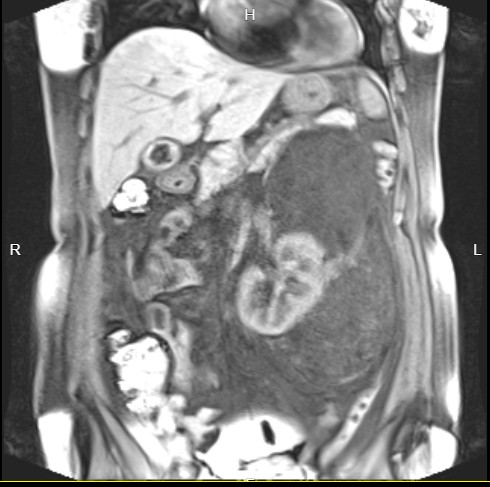

图片发自160App

腹膜后血管平滑肌脂肪瘤的基本概述

腹膜后血管平滑肌脂肪瘤是一种较为少见的良性肿瘤,它主要由平滑肌、血管及成熟型脂肪细胞这三种组织学成分构成。该肿瘤可发生在0~77岁的任何年龄,且无明显性别差异。

|磁共振|在发现肿瘤范围及其与周围组织和血管的关系时,优于CT||